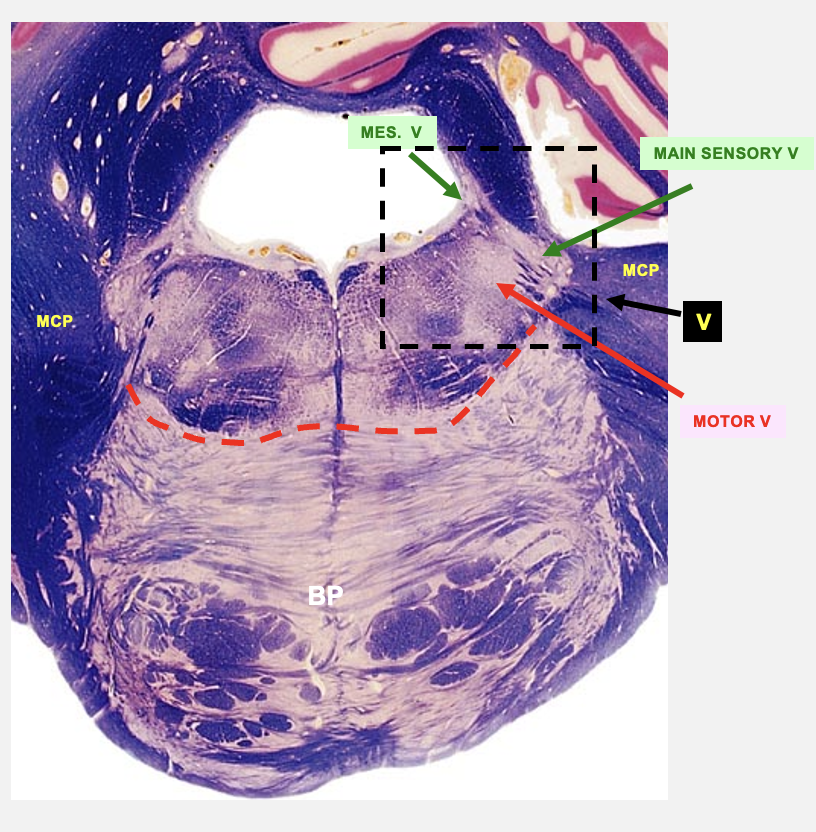

trigeminal nucleus

cranial nerve 5; general/somatic sensory conveying information on touch, pain, propioception from the face

composed of three nuceli

main sensory nucleus

spinal nucleus

mesencephalic nucleus

three nuceli that make up the trigeminal nucleus

touch and pressure from all three divisons of CN 5

pain and temperature from all divisions of CN 5

proprioceptioin from muscles of mastication and mechanoreceptors in teeth and jaw

motor V

cranial nerve 5; branchial motor - nucleus that gives rise to axons that innervate muscles of mastication

motor nucleus of V

main sensory nucleus of V

mesencephalic nucleus of V

rostral pons cross-section structures

trigeminal nerve

motor trigeminal nucleus

the axons of the BLANK BLANK separate the BLANK BLANK BLANK from the BLANK BLANK BLANK

basilar pons